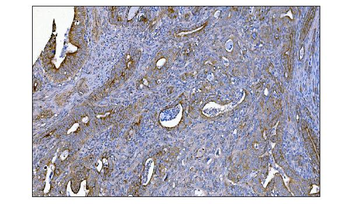

IHC staining of FFPE human colon carcinoma with MerTK antibody (clone TPKR-1). HIER: boil tissue sections in pH9 10mM Tris with 1mM EDTA for 10-20 min and allow to cool before testing.